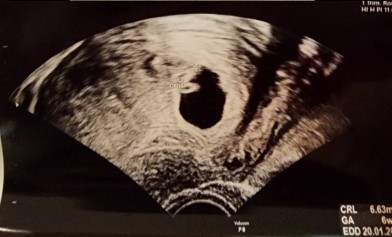

อันนี้ตอน 7+4 วีคค่ะ เห็นหัวใจกระพริบแต่ยังไม่ได้ยินเสียง ตอนนี้ 26+1 แล้วจ้า

มีแค่ถุงกับไข่แดงค่ะ